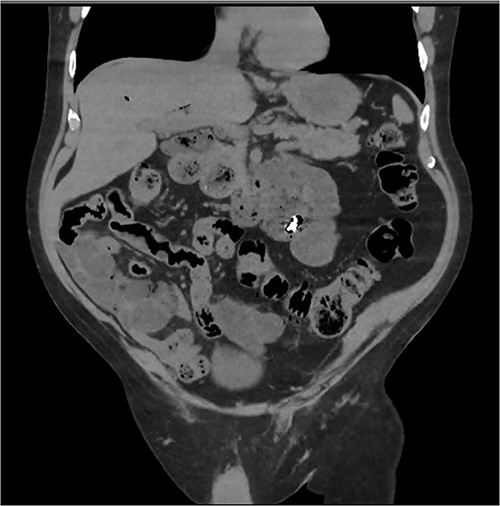

An 80 year old male presented to the emergency department after accidentally swallowing his hearing aids. On presentation he was pain free, hemodynamically stable, and had a soft abdomen. He had a background of type-2 diabetes, rheumatoid arthritis and diverticulitis. The hearing aids were powered by lithium battery. X-ray found two foreign bodies in the left upper abdomen (Fig. 1). After assessment in the emergency department, he returned home to await their natural passage. One hearing aid was found in his stools the following day, but he represented three weeks later as the second hearing aid remained unaccounted for. He underwent repeat abdominal x-ray and CT, which found the hearing aid retained within a presumed distal duodenal diverticulum (Figs 2 and 3). He was booked a push enteroscopy the following day.

Abdominal CT identifying one hearing aid in a jejunal diverticulum 3 weeks after initial presentation – coronal view.